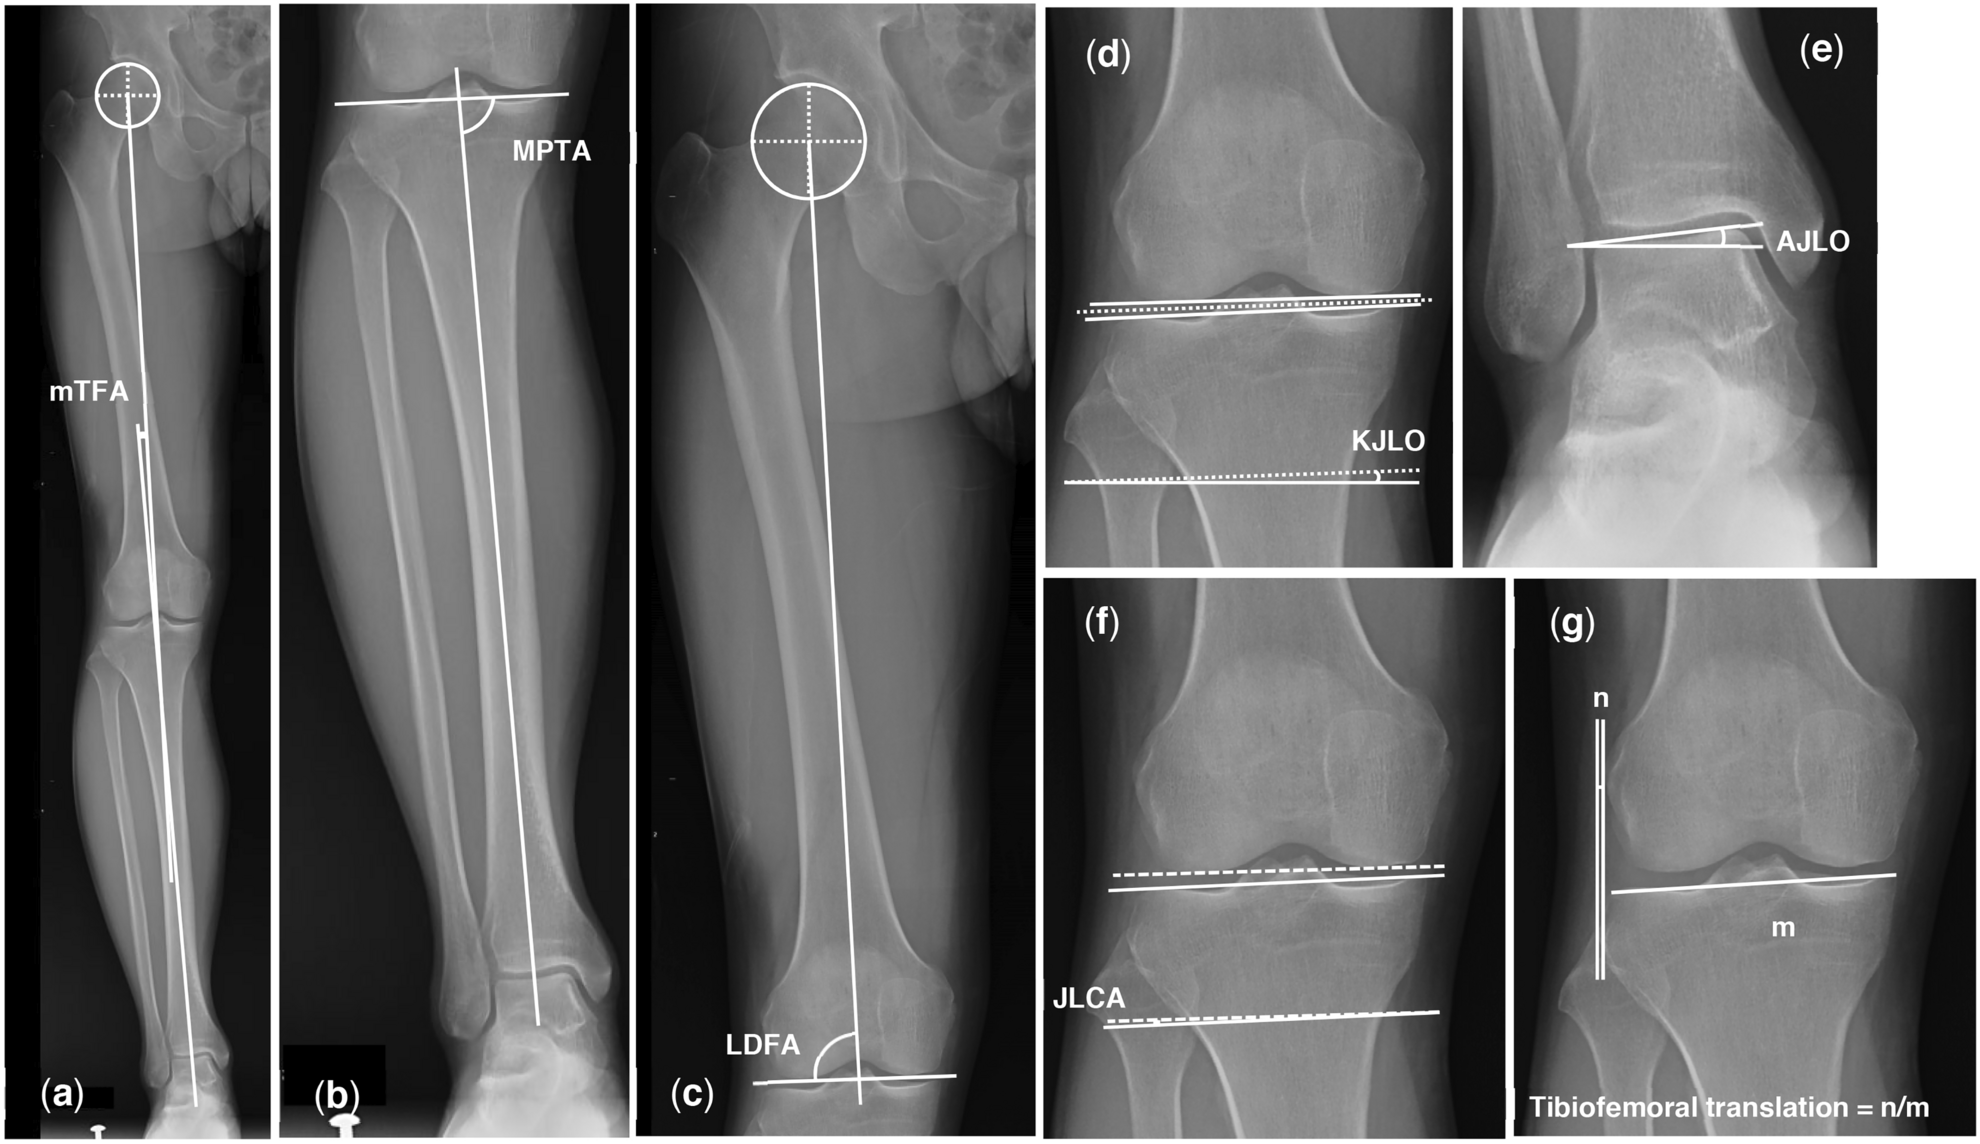

Fig. 1

Measurement of mTFA, MPTA, LDFA, KJLO, AJLO, JLCA, and tibiofemoral translation. (a) mTFA (b) MPTA (c) LDFA (d) KJLO (e) AJLO (f) JLCA (g) Tibiofemoral translation. mTFA mechanical tibiofemoral angle, MPTA medial proximal tibial angle, LDFA lateral distal femoral angle, KJLO knee joint line orientation, AJLO ankle joint line orientation, JLCA joint line convergence angle.